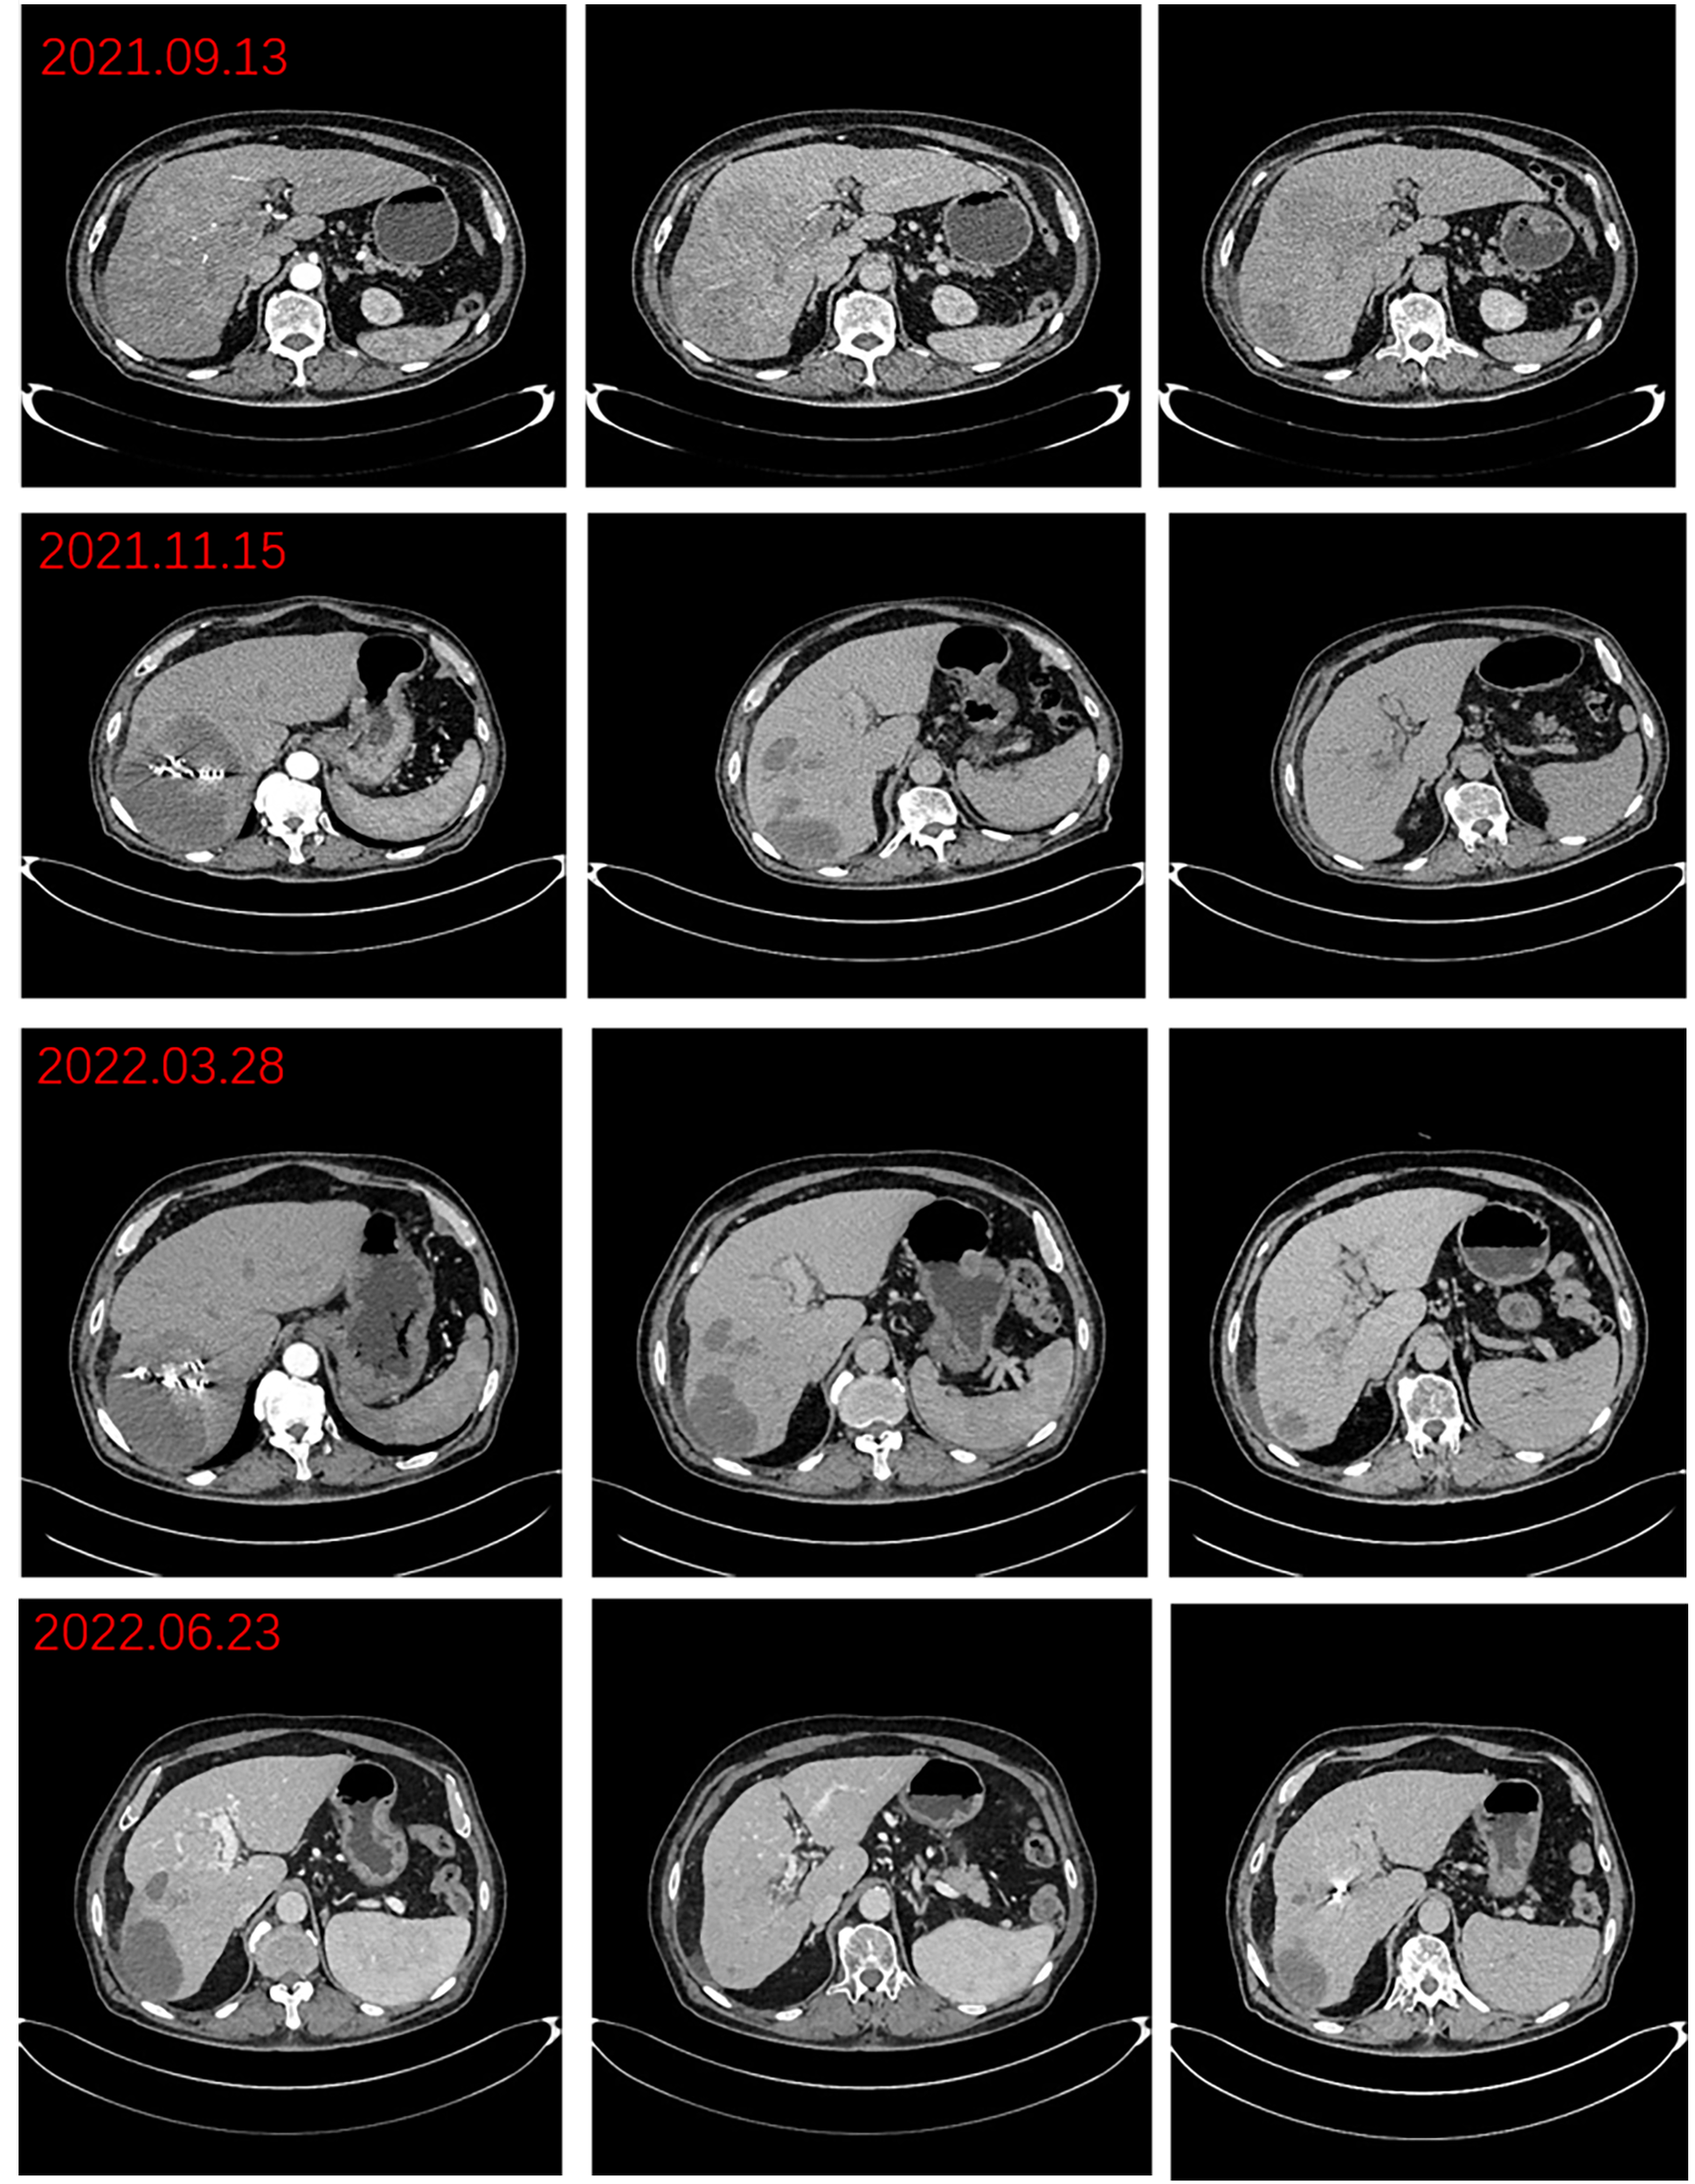

The patient was a 76-year-old male who presented to Lanzhou University First Hospital on August 5, 2021, with upper abdominal bloating and mild pain persisting for over one month. He reported no other symptoms, and an abdominal ultrasound conducted at another local hospital indicated the presence of a liver mass. His medical history included chronic hepatitis B for over 30 years, hypertension, diabetes, and cataract surgery with intraocular lens implantation. Upon physical examination, the patient exhibited normal skin and mucosal color without jaundice, a flat abdomen devoid of abdominal wall varices, and no remarkable gastrointestinal contour or peristalsis. There was no tenderness upon abdominal palpation, and the liver was palpable below the rib margin. Murphy’s sign was negative, and bowel sounds were noted at a rate of four times per minute. Laboratory tests revealed the following values within normal limits: white blood cell count (WBC: 5.03 × 10^9/L), neutrophil ratio (NEUT%: 68.8%), hemoglobin (HGB: 124 g/L), and platelet count (PLT: 205 × 10^9/L). Tumor markers were elevated, including alpha-fetoprotein (AFP: 289 U/mL), carbohydrate antigen 19-9 (CA 19-9: 109 U/mL), carcinoembryonic antigen (CEA: 1.4 ng/mL), and ferritin (519 ng/mL). Biochemical analysis indicated that aspartate aminotransferase (AST: 67 U/L), alanine aminotransferase (ALT: 216 U/L), total bilirubin (TBIL: 16.4 µmol/L), direct bilirubin (DBIL: 4.8 µmol/L), alkaline phosphatase (ALP: 216 U/L), gamma-glutamyl transferase (GGT: 371 U/L), and glucose (GLU: 6.59 mmol/L) were outside normal ranges. Tests for hepatitis B (2+, 5+) and hepatitis B virus DNA (HBV DNA < 100 IU/mL) were negative. Brain natriuretic peptide (BNP: 143.4 pg/mL) was outside the normal range. The enhanced abdominal CT scan revealed a large mass-like abnormal enhancement in the right lobe of the liver, suggesting hepatocellular carcinoma (HCC) with portal vein thrombosis in the main trunk as well as the left and right branches, cirrhosis, and portal hypertension (including esophageal and gastric fundus varices). Magnetic resonance imaging (MRI) of the liver revealed a large abnormally enhanced mass in the right lobe, suggesting hepatocellular carcinoma (HCC) with intratumoral hemorrhage and portal vein thrombosis in the main trunk as well as the left and right branches; cirrhosis, splenomegaly, a small amount of ascites, liver disease, and gallbladder disease (Figure 1). The patient was diagnosed with HCC of the right lobe, post-hepatitis B cirrhosis, grade 3 hypertension (very high risk), and type 2 diabetes, classified as stage IIIa according to the CNLC staging system (Figure 2). An initial multidisciplinary team (MDT) discussion resulted in a treatment plan that included hepatic artery infusion chemotherapy (HAIC) treatment (FOLFOX), combined with 200 mg sintilimab and sorafenib 0.4 g bid targeted therapy. The patient was discharged on August 16th, 2021. After discharge, oral sorafenib 0.4g bid targeted therapy was prescribed. On the second admission, a second MDT discussion was held to adjust the protocol: HAIC treatment and percutaneous liver puncture for radioactive 125I particle implantation, combined with 200 mg sintilimab and sorafenib targeted therapy. After the fifth admission, there was no significant change in the portal vein tumor thrombus. The third MDT was conducted, and on March 29, 2022, “percutaneous hepatic puncture radioactive 125I particle implantation” radiation therapy was performed. Additionally, because the patient could not tolerate bisphosphonates, the treatment was changed to once-daily targeted therapy with 8 mg of lenvatinib. The patient underwent abdominal CT (plain + enhanced) at the sixth admission on June 21, 2022, compared with the previous scan on March 28, 2022 showed a lesion in the right lobe of the liver with little change, along with occlusion of the main portal vein and portal spongiosis, which remained little changed from the previous scan (Figure 2). After comprehensive consideration of the timing of surgical resection following successful conversion, the decision was made to perform surgical treatment. Subsequently, another preoperative evaluation was conducted, which included gastroscopy, revealing a 0-Ia+IIc type lesion can be seen near the anterior wall of the cardia, with a size of about 3 × 2 cm and chronic atrophic gastritis (Figure 3A). After the fourth MDT, the gastric tumor was initially resected via laparoscopy combined with endoscopy under general anesthesia on July 4, 2022 (endoscopic mucosal resection, partial gastrectomy, and D1 lymph node dissection). Due to the patient’s poor cardiopulmonary function during the operation, the laparoscopic surgery was interrupted and converted into an open procedure for right hepatectomy and cholecystectomy (Figure 3B). The postoperative gastric histopathology report indicated ectopic hyperplasia of adenoepithelial hyperdifferentiated epithelial endothelium and focal carcinomatous lesions (Figure 3C). Two trans arterial chemoembolization (TACE) procedures were performed on September 13, 2022, and April 3, 2023, as adjuvant treatment following hepatic resection, in accordance with the Guidelines for the Diagnosis and Treatment of Primary Hepatocellular Carcinoma (2022 edition). Postoperative abdominal CT and MRI were performed on December 18, 2023, which revealed the disappearance of the portal vein thrombus and widening of the hepatic fissure (Figure 4). Remarkably, the patient demonstrated a favorable prognosis, recovering well and remaining free of tumor recurrence or metastasis during over eight months of follow-up.

Figure 2

Preoperative imaging changes of hepatocellular carcinoma lesions.